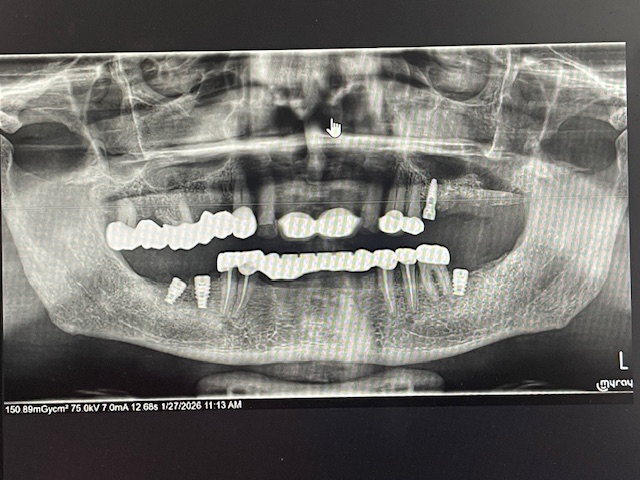

Would like feedback on implant #3. Angulation is not ideal but still restorable.

Would an angled abutment probably be required?

i think you should be fine w/ a screw retained straight stock abutment

the access hole will be more mesial but should be fine.

go ahead and take impression when implant is ready, send to lab.

the angulation is not the best but should be restorable w/ a straight stock (prefab) abutment. IMO

I would suggest that you not be so hard on yourself because that placement is fine… It is actually perfectly in line with the molar and it would require ortho in order to satisfy the goal of being perfectly parallel to the mesial and distal tooth. Don’t be so hard on yourself.

Your placement is excellent. Perfection is unachievable but we are constantly striving for that